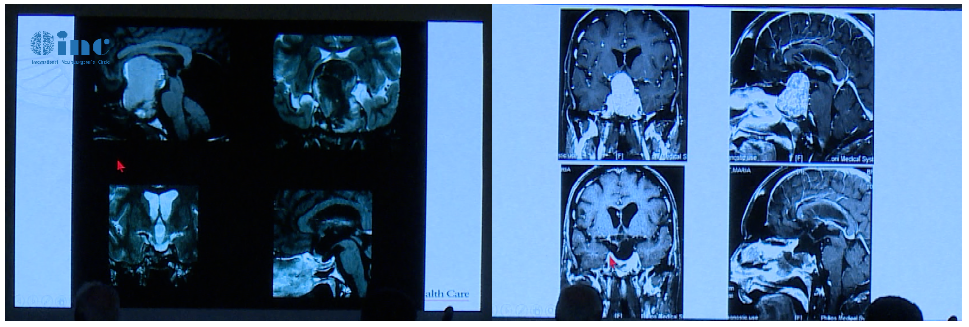

Couldwell教授演讲中展示的部分较大垂体瘤

患者术前情况:62岁女性,患者35年前有垂体大腺瘤复发史,随后接受放射治疗复发性肿瘤引起的侧性眼球麻痹的进行性复视。

术后影像片子显示肿瘤切除干净:

术前影像显示肿瘤较大:

术后影像,肿瘤体积明显缩小

术后影像: